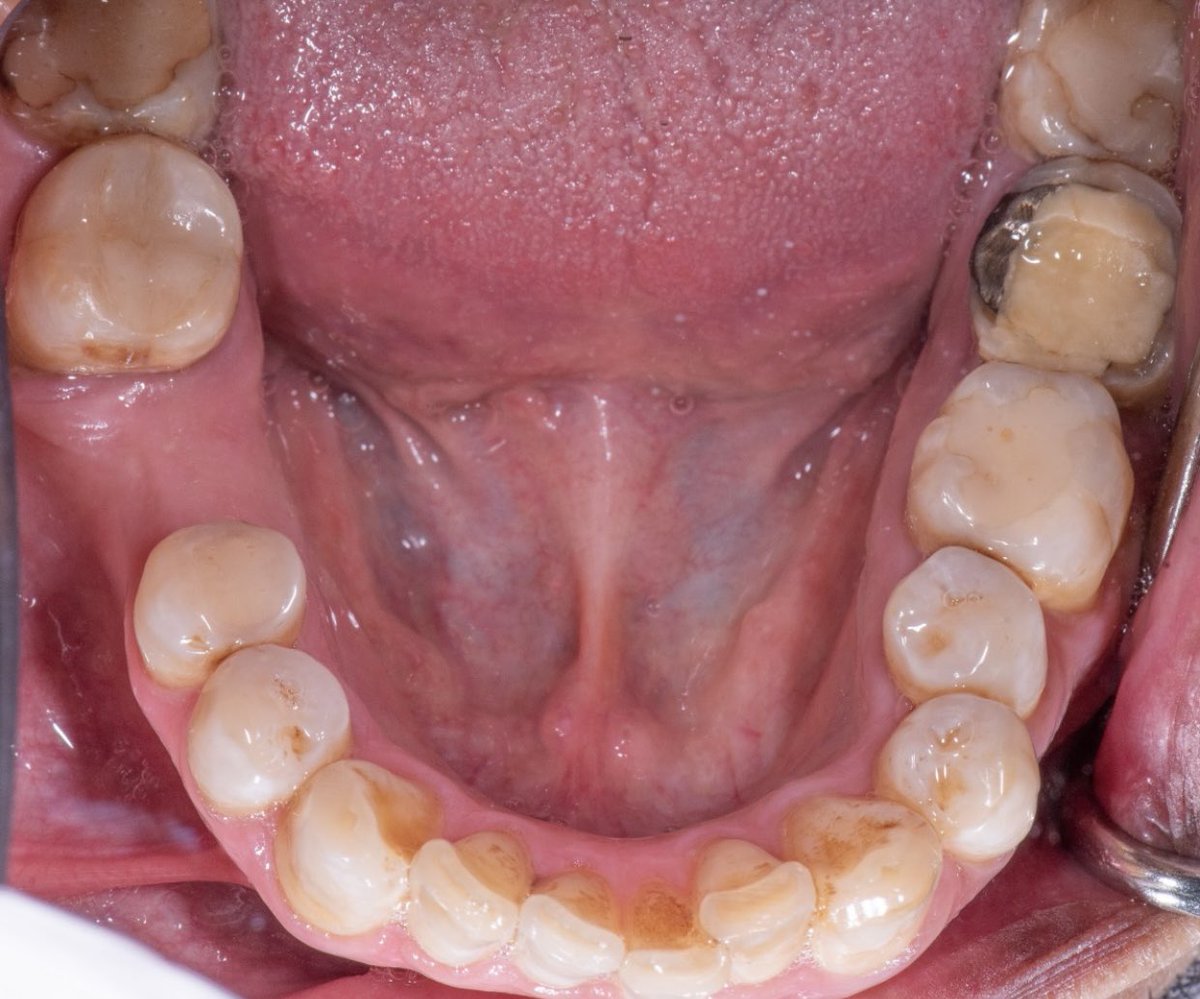

Zirconia crown on Endotreated #47 Implant supported crown on #46, The implant was placed by @alomar_ahmed